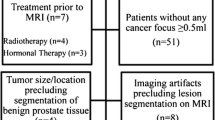

For a training dataset, between January 2017 and February 2019, a total of 267 patients were histologically confirmed as prostate adenocarcinoma by radical prostatectomy or non-targeted systematic biopsy. Among them, 111 patients who fulfilled the inclusion criteria were enrolled in the training dataset. The inclusion criteria were as follows: (a) patients having undergone preoperative or post-biopsy 3T-MRI and (b) patients with data on GS. Among the 111 patients, 46 were excluded for the following reasons: (a) previous treatment (hormone therapy, radiation therapy or radical prostatectomy) for PCa (n = 20), (b) marked metallic artifact on MR images (n = 2), (c) transurethral resection of the prostate (n = 8), (d) no identified focal lesion on T2WI and DWI (n = 16). Finally, 65 patients (mean age: 69 years, range 51–88 years) were enrolled in the training dataset (Fig. 1).